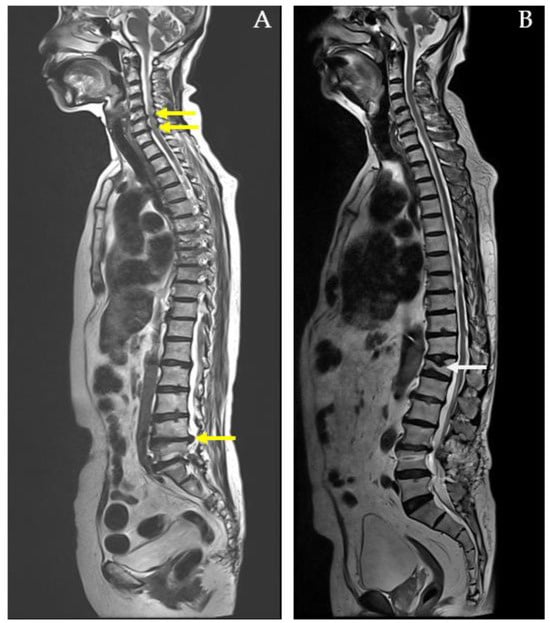

This research is important because it provides a pathway to more accurate, efficient, and cost-effective diagnostics for spinal conditions, enhances clinical decision-making, and contributes to the broader integration of machine learning into personalized healthcare. Furthermore, the study did not account for complex cases, such as those depicted in Figure 4, where patients presented with both pathological compression fractures and diffuse bony metastases, or with multiple spinal conditions like spondylolytic spondylolisthesis.

While the SVM model provides useful classification results, its lack of interpretability in comparison to simpler models like logistic regression may limit its clinical utility. Clinicians may require more transparent models that provide clear explanations for their predictions. Thus, future work could focus on developing interpretable machine learning models that offer high accuracy without sacrificing transparency. Furthermore, the study did not account for complex cases, where patients presented with both pathological compression fractures and diffuse bony metastases, or with multiple spinal conditions like spondylolytic spondylolisthesis. These more complicated cases were not fully addressed in the model, which could limit its application in more severe or multifactorial clinical scenarios. Future studies should incorporate these complex cases to improve the model’s comprehensiveness and clinical relevance.

Figure 4. MRI whole-spine imaging demonstrating pathological compression fractures, herniated intervertebral discs (HIVDs), and spondylolisthesis indicated by yellow arrows. In (A) a 59-year-old male diagnosed with lung cancer and diffuse bony metastases affecting the cervical, thoracic, lumbar spine, sacrum, bilateral iliac bones, and right femoral head. The MRI reveals a pathological compression fracture of the T5 vertebral body with associated spinal cord compression. Additionally, herniated intervertebral discs (HIVDs) are present at the L3-L4, L4-L5, and L5-S1 levels. In (B) an 87-year-old female with a compression fracture at the T8 vertebral body. The MRI also shows L5-S1 spondylolytic spondylolisthesis with narrowing of bilateral neural foramina.